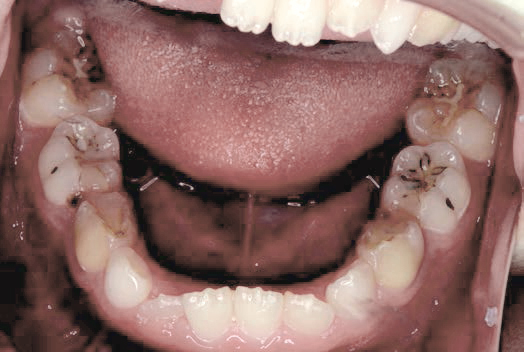

Before

歯がガタガタに並んでいて、前歯の真ん中の位置が少し左にずれていました。

奥歯が生えるためのスペースが足りず、永久歯が生えて来られない状況が確認できました。

また、飲み込むとき下くちびるに力が入ってしまうクセが見られ、お顔全体の成長が遅れている様子が確認できました。

治療を終えて

歯がきれいに生えるためのスペースをしっかり確保することができ、歯並びを乱していたお口のクセも改善されたため、奥歯が生えるスペースを確保することができました。

しっかり噛めるかみ合わせを作ることが、将来の健康につながるので「よく噛む」練習も続けてもらっています。

主訴・治療内容 歯がガタガタになってきたことに悩み、無料相談に来院されました。

治療期間 3年

費用 462,000円(税込)